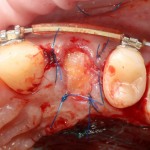

В этом случае мы используем Mucograft Seal как наименее травматичный и наиболее простой способ герметизации лунки:

Матрица подшивается узловыми швами к краям лунки, таким образом достигается ее герметичность:

И вот что важно про швы. Любые другие способы подшивания что матрицы, что десневого лоскута, например П-образные или Х-образные швы, во-первых, не обеспечивают нужной герметичности, а во вторых создают излишнее натяжение краев слизистой оболочки, что приводит их деградации и стимулирует атрофию тканей. Так что лучше потратить побольше времени и зашить лунку так, как надо, чем потом переживать за результат операции.